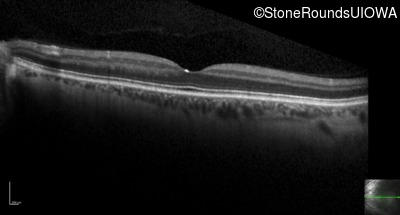

Optical Coherence Tomography - Right - 20/200

Exemplar / OCT Stack

OCT Stack